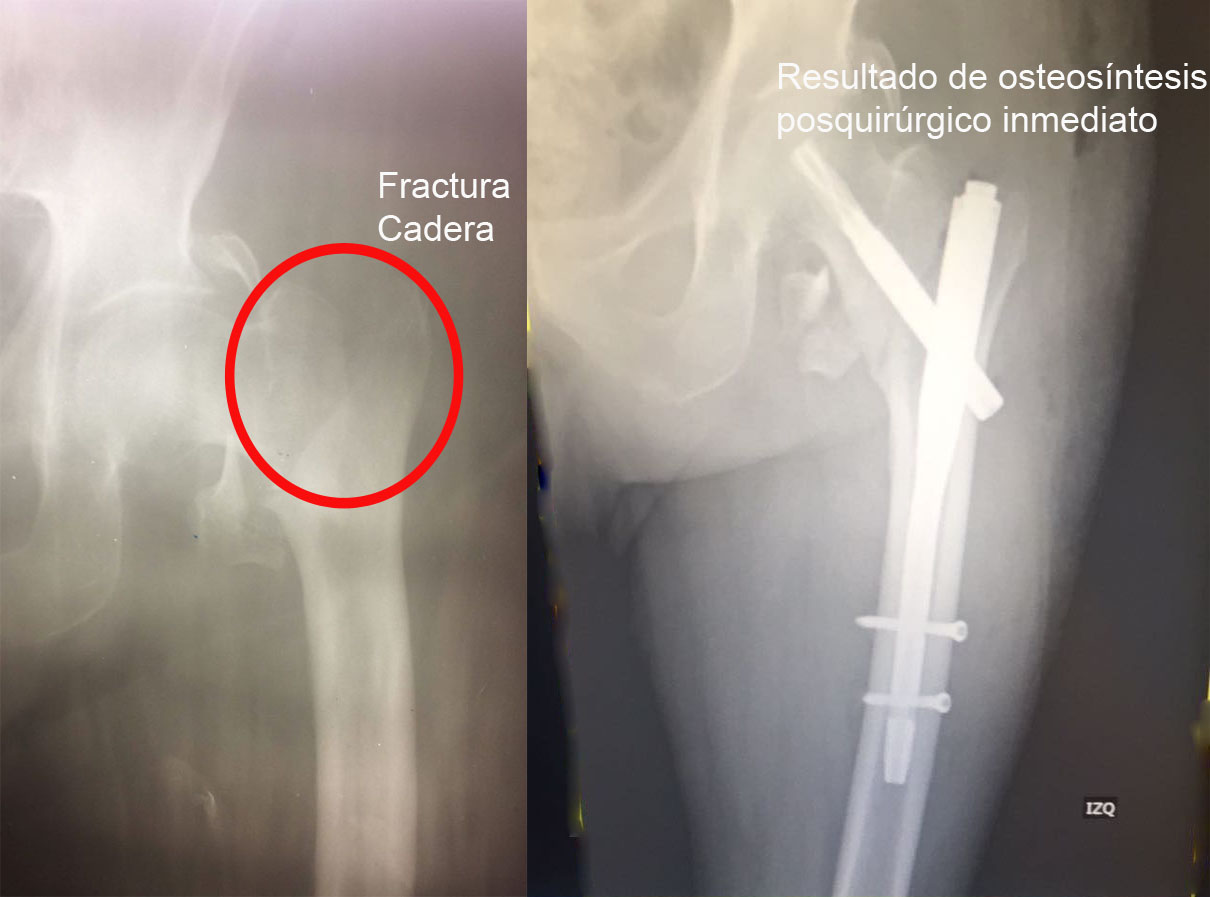

Una fractura ósea es la ruptura de un hueso, la cual puede presentarse por diversas causas y su tratamiento dependerá de la magnitud, sitio anatómico y de las enfermedades concomitantes. Algunas pueden manejarse de forma conservadora con solo inmovilización y hay otras que requieren de un tratamiento quirúrgico. A continuación, podrá ver algunos casos quirúrgicos, dando clic a la zona del cuerpo afectada.